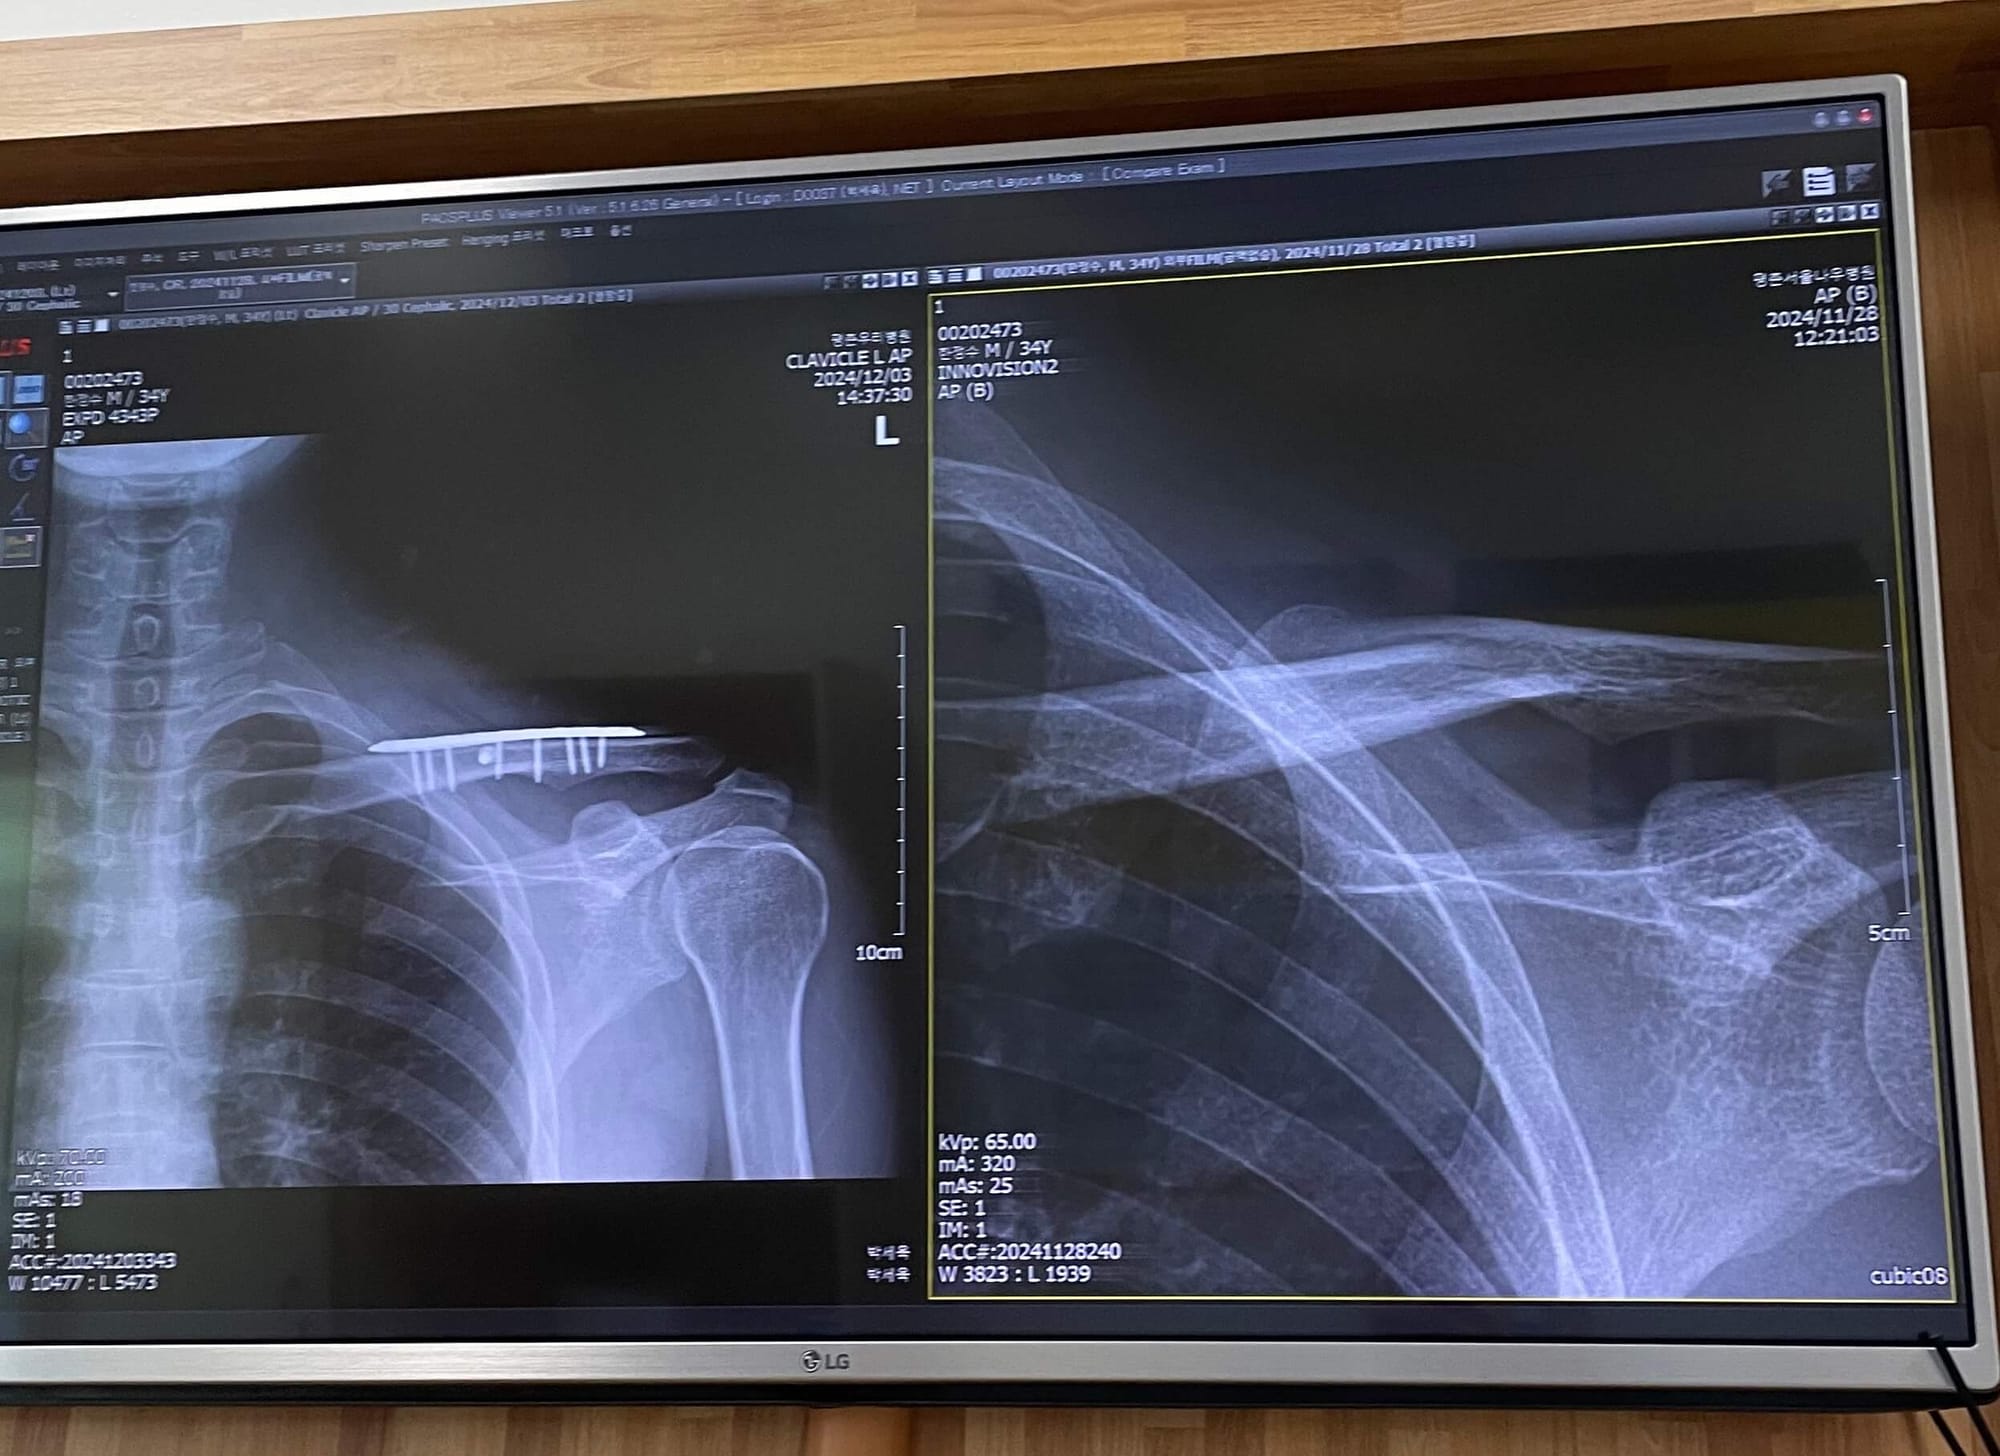

그렇게 매주 행복 축구를 해왔는데 11월 어느 날 가슴팍에 고프로 카메라를 처음으로 착용하고 경기에 뛴 나는, 카메라를 의식했는지 생전 해보지도 않은 오버헤드킥을 시전했다.

그 결과, 어깨로 착지해서 쇄골이 골절되었고, 12월 초에 한국에 가서 쇄골에 철심을 박아 고정하는 수술을 받았다. 멍청..🫠

수술 후에는 암슬링을 하고 있어서, 수지와 지호보다 손이 많이 가는 와이프의 큰아들로서 큰 짐이 되고 있다. 미안하고 사랑해 여보 😅